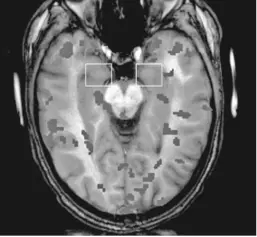

Как побудить людей сразу довериться нам? Какие особенности мозга заставляют нас верить в то, что не соответствует истине? Как побеждать в спорах, используя тактику новорожденных младенцев?